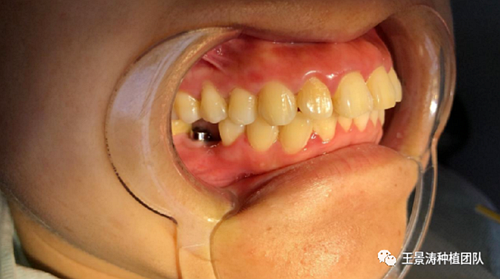

左側(cè)下頜第二磨牙及右側(cè)下頜第一磨牙同時即刻種植病例。患者年輕女性,無系統(tǒng)性疾病。37及46殘冠及殘根,且46劈裂,無法冠修復(fù),必須拔除。37根尖慢性炎癥,大量肉芽組織存在,46根分叉較高,根分叉骨質(zhì)尚可。CBCT示:根尖骨質(zhì)至下牙槽神經(jīng)管距離可滿足種植體的初期穩(wěn)定性,遂考慮即刻種植,并在種植體周邊填入骨粉并覆蓋骨膜,雙側(cè)的種植體初期穩(wěn)定性相差無幾,但考慮到37根尖慢性炎癥較大,遂給予埋入式種植。

術(shù)后一周的口內(nèi)照片